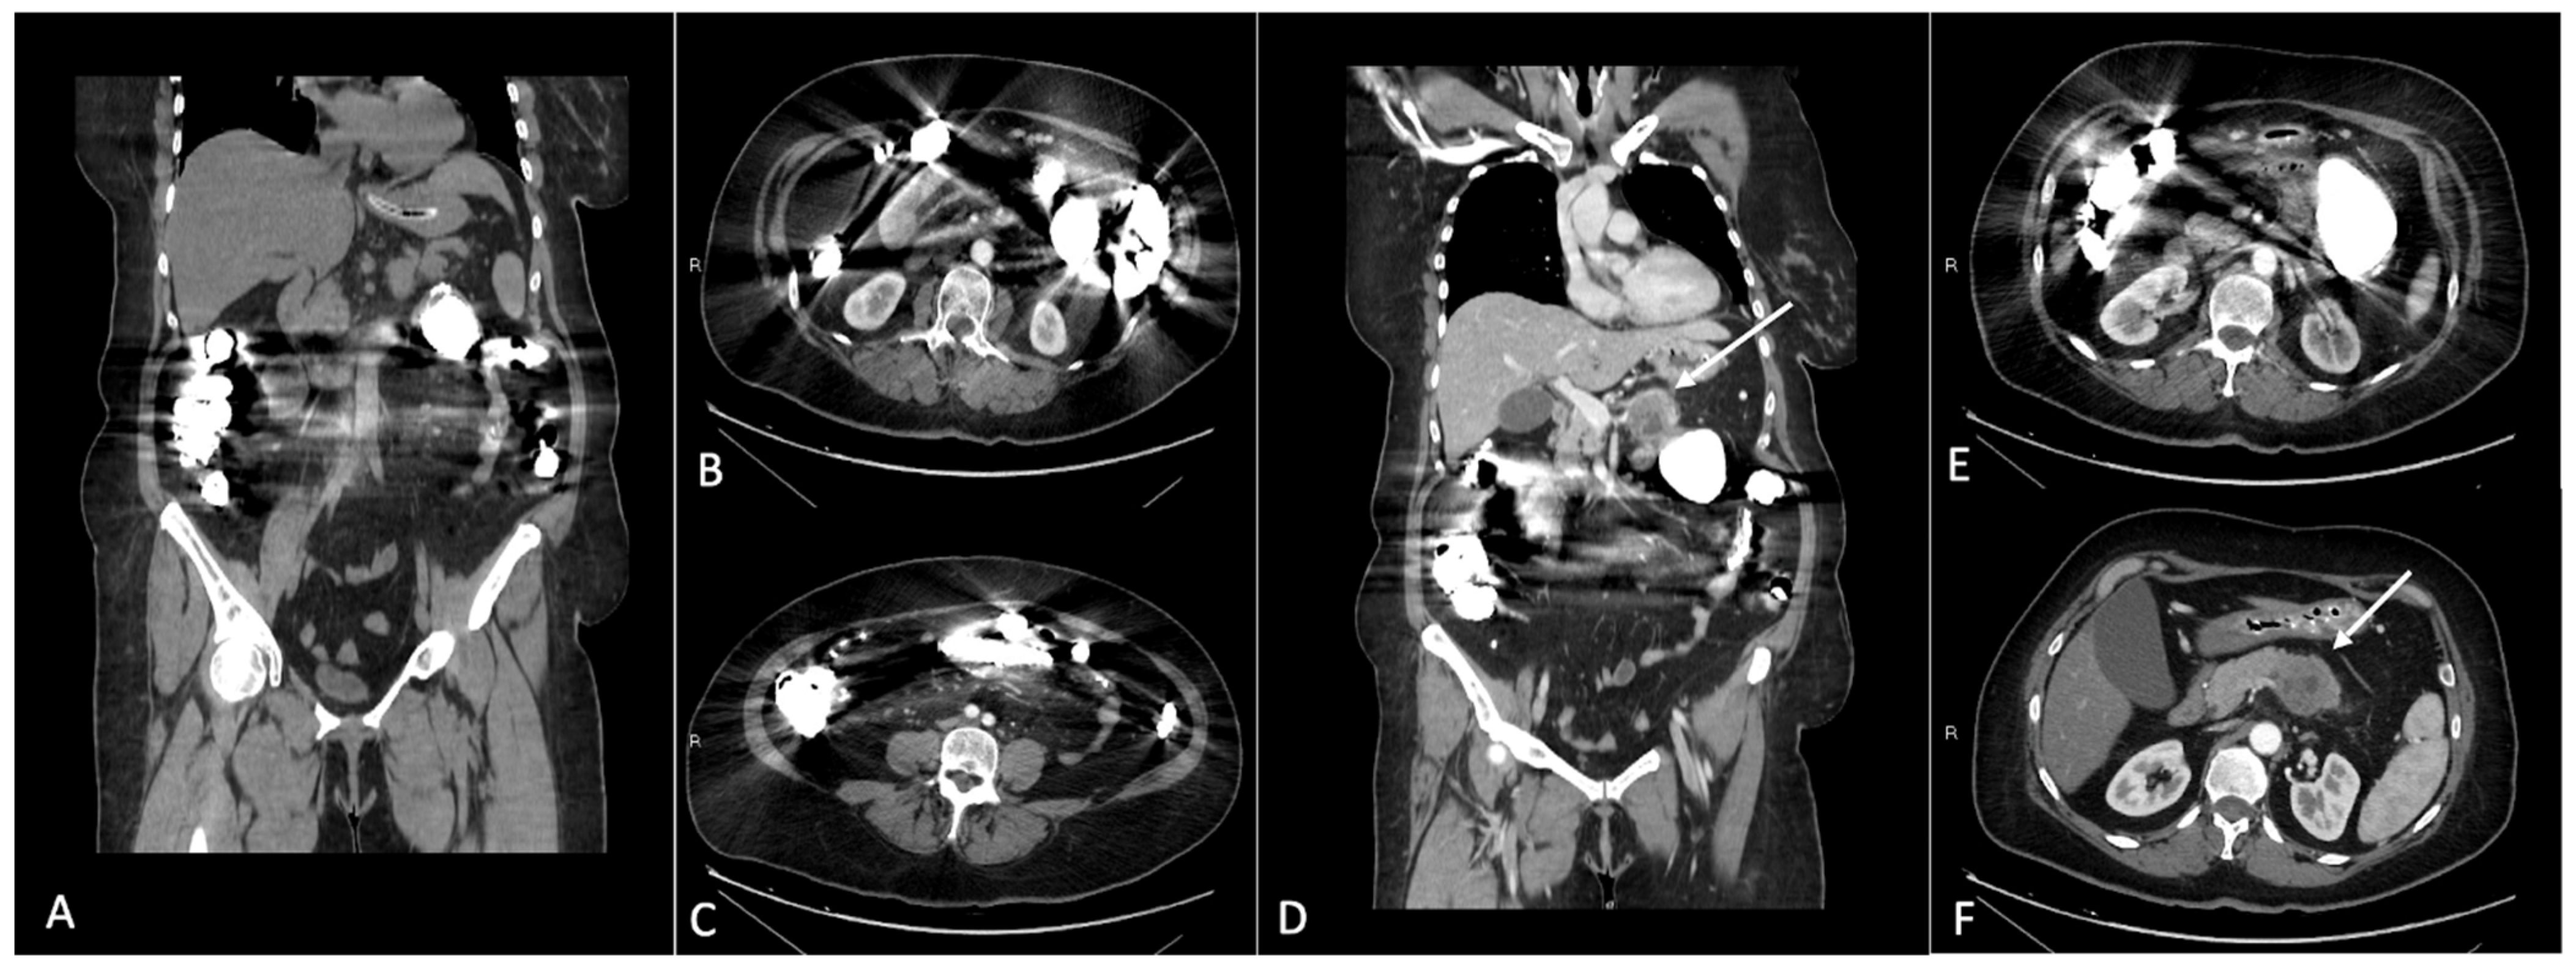

Figure 1. (AC) Coronal and axial CT images after iodinated contrast medium intravenous injection in a patient with gadolinium accumulation in the bowel loops. Images show the streak artifacts generated by the presence of gadolinium contrast medium in the lumen of intestinal loops. (DF) Please note the decreased imaging resolution of the pancreatic region. In (D,F), it is possible to identify a pancreatic solid mass in the body of the pancreas (arrows); the presence of the artifacts related to gadolinium in the bowel loops makes the evaluation of the pancreatic mass suboptimal.